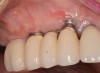

When dental implants fracture, they typically require removal. Implant fracture can lead to abutment instability and screw loosening, which may result in inflammation and infection as subgingival bacteria colonize normally inaccessible regions. This can lead to marginal and buccal/facial bone loss associated with the location of the fracture. When the coronal aspect of a restored implant fractures, it can cause mobility of the abutment and cemented restoration (Figure 1). In addition, multiple try-ins of ill-fitting restorations and torqueing of abutment screws can fracture an implant (Figure 2). Bone loss, swelling, and discomfort persisted after localized debridement and systemic antibiotic therapy; therefore, this implant was eventually removed.

(2.) The implant is fractured, and significant bone loss is evident. This implant required removal and site augmentation to facilitate new implant placement.

Figure 2